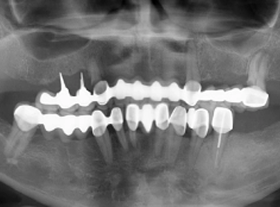

Mất nhiều răng hàm trên. Màu răng ố vàng, hình thể răng không đều

• Cấy ghép Implant All On 6 hàm trên

• Bọc răng sứ toàn hàm dưới